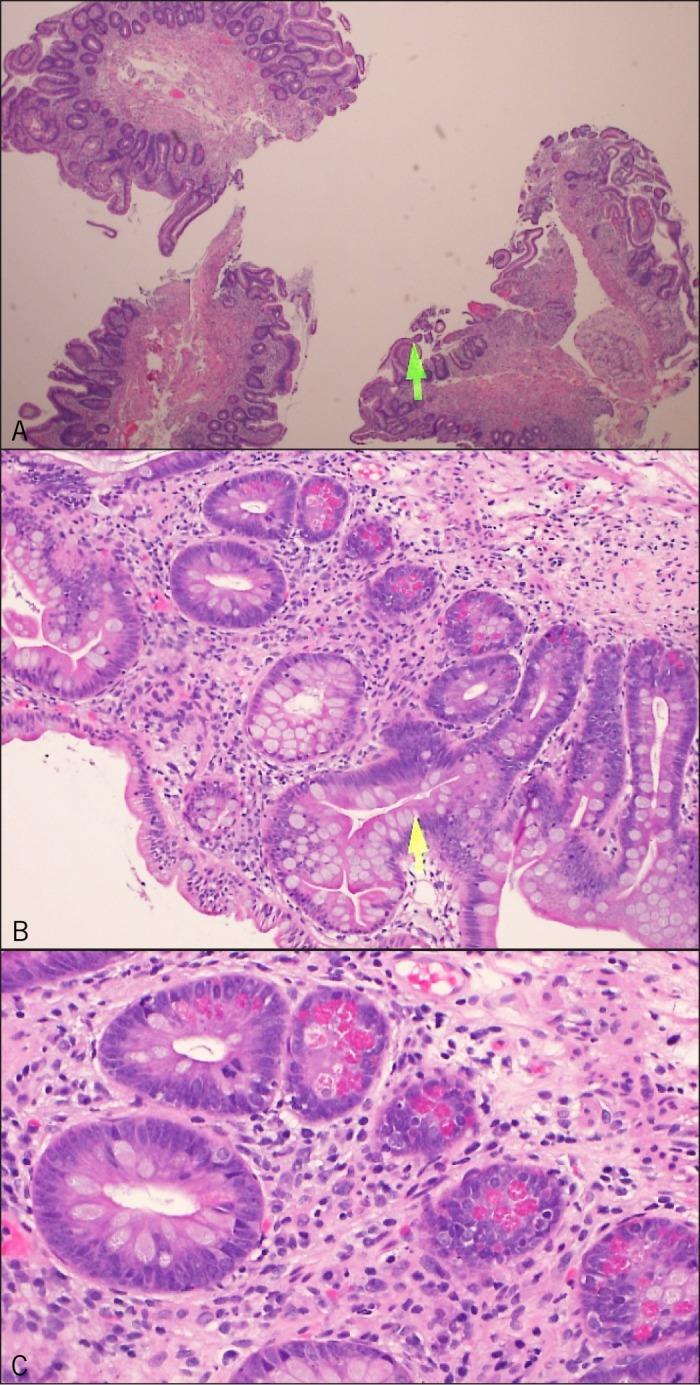

Graft-Versus-Host Disease of the Upper Gastrointestinal Tract After an Autologous Stem Cell Transplant.

Graft-versus-host disease (GVHD) in recipients of autologous stem cell transplantation (SCT) is less common compared to recipients of allogeneic SCT, but its existence has been well documented. Similarly, the diarrheal component of the disease is highlighted when discussing its gastrointestinal (GI) manifestations, with less emphasis given to upper GI symptoms like nausea and vomiting. We present a case illustrating the upper GI tract signs and symptoms of GVHD after autologous SCT, and emphasize that prompt treatment can rapidly improve morbidity and prevent disease progression.